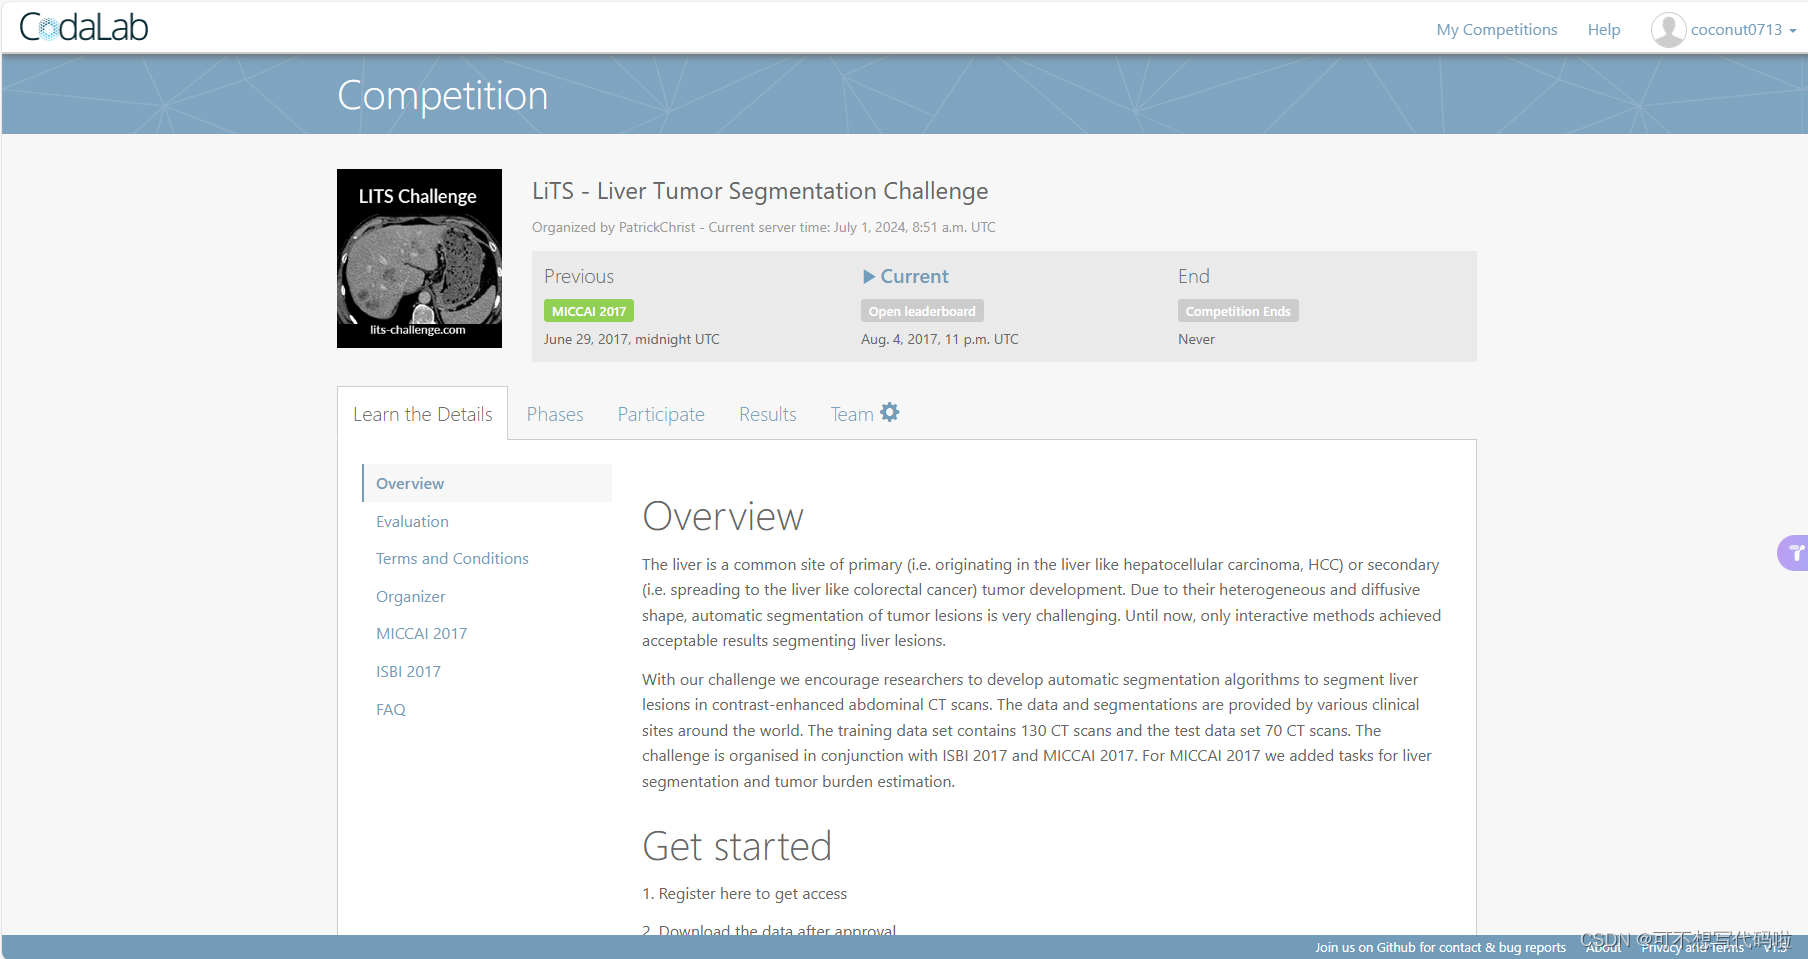

LiTS (The Liver Tumor Segmentation Benchmark) 是专注于肝脏及其肿瘤分割的 CT 数据集。该数据集收集了 7 个不同医学中心的数据,包含 131 例训练集和 70 例测试集,其中测试数据标签不公开。LiTS训练集中包含3DIRCADB中的所有数据,所以不要合并这两个数据集。

基于该数据集,已在 ISBI 2017,MICCAI 2017 和 MICCAI 2018 都成功举办了相关竞赛,并被 MSD (Medical Segmentation Decathlon) 收作 Task03 子任务。

注册账号并登录,然后在Praticipate-Get Data中会提供下载链接(需要科学上网)。